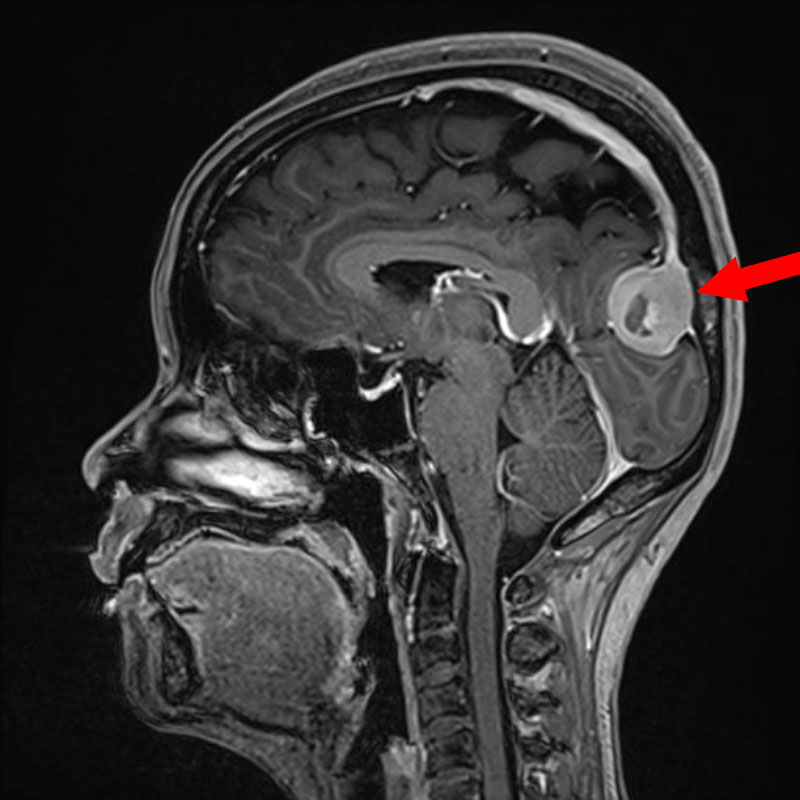

断層撮影

手術前1

手術前2